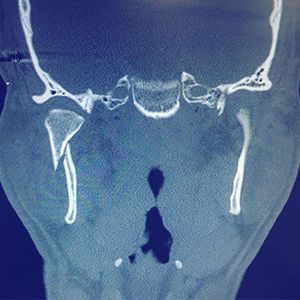

Subcondylar fracture of the mandible, this type of trauma is often caused by a fall or being punched in the face 👊